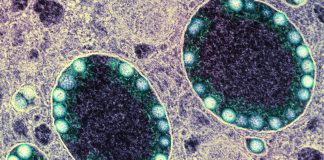

COVID-19 è una malattia infettiva respiratoria causata dal virus denominato SARS-CoV-2 appartenente alla famiglia dei coronavirus. Una malattia infettiva causata da un nuovo virus mai identificato prima negli esseri umani.